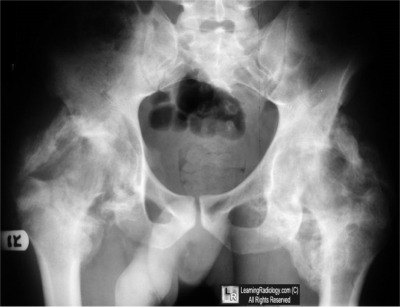

Frontal Radiograph of Pelvis

4. Heterotopic ossification

Heterotopic ossification

- Defined as the abnormal formation of true bone within extra-skeletal soft tissues

- More common in males, especially following spinal cord injury, it is rare in young children

- Formerly called myositis ossificans

- That term has fallen out of favor because the condition is not always inflammatory and ossification occurs in soft tissues other than muscle

- Strong association exists between HO and spinal cord or traumatic brain injury

- About 20-30% of patients with neurologic deficits will develop HO, possibly higher with spinal cord injuries

- It is also seen in burn patients, following surgery, and following blunt trauma such as horse riders may develop in the adductor muscles of the leg

- There is an increased risk for HO in patients with Diffuse Idiopathic Skeletal Hyperostosis (DISH) and Paget’s Disease